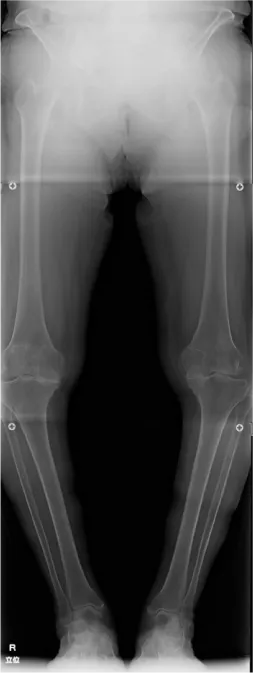

変形性膝関節症が最も多い疾患で、それに伴う半月板損傷やその他リウマチの患者さまが多くおられます。年代としては60代から80代までの方が一番多く、中には50代や90代の方で人工膝関節手術を受けられる方もおられます。

人工膝関節置換術

人工膝関節置換術は、傷んだ関節表面を切除し、金属やセラミック、ポリエチレンなどで作られた人工の関節に置き換える手術です。虫歯を削って被せ物をするような手術です。現在日本では年間9万件以上行われているといわれています。

近年、人工膝関節置換術は、人工関節自体のデザインや素材が飛躍的に良くなり、また手術方法の発達により、15〜20年以上長期間でも約90%が入れ替えを必要としないで済むと報告されています。

• O脚膝 術前

• 人工関節置換術後